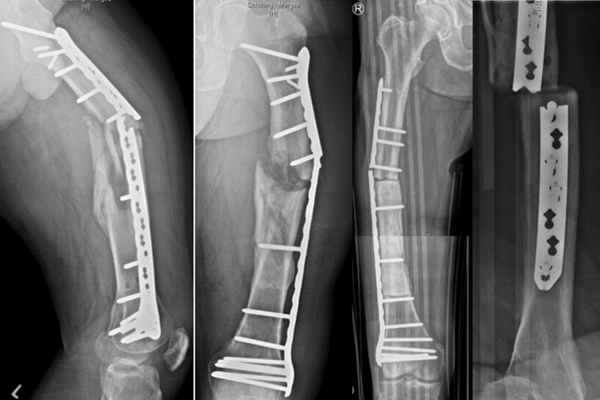

FAILED FRACTURE FIXATION